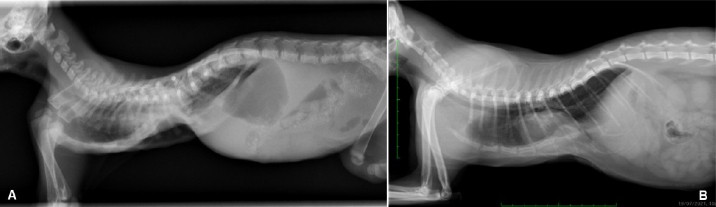

Fig. 7. Transverse CT scan of the cat’s chest at the level of the xiphoid process, soft tissue window view (A), and bone window view (B).

The cat in this report was 3 months old and, based on the pectus severity index, had a severe pectus excavatum; therefore, an external splinting technique with a 3D-printed cast, customized on the base of CT images was chosen. CT scan was useful to better assess skeletal deformities, anomaly of the intrathoracic structures, and safe corridors for the needle passage. Moreover, CT was fundamental to design the splint. Five sutures were applied, the most caudal three being gradually pulled outward the concave part of the sternum and the other two directly ligated to the splint. The decision to surgically approach the seventh sternebra and xiphoid process to place the corresponding suture under direct vision was taken based on the result of the CT scan. CT images showed a close relationship between the seventh sternebra and the xiphoid process (Fig. 7), with the aorta and caudal vena cava occupying most of the thoracic space, making blind passage of the needle too risky. With this approach, the skeletal segment could be grasped and pulled ventrally, increasing the space for a secure passage of the needle. There were no surgical complications such as organ laceration or puncture, nor postoperative complications such as re-expansion pulmonary edema. The concern of the development of the re-expansion pulmonary edema, based on the sudden increase of the intrathoracic pressure due to the correction of the sternal concave deformity, lead the authors to the decision to gradually correct the sternal deformity. In this way, the increase in intrathoracic pressure and, therefore, lung re-expansion occurred little by little, reducing the risk for this complication. For these reasons, the sutures were gradually tightened during the first 2 weeks in response to the skeletal development of the kitten, and then kept in place for further 2 weeks to allow consolidation. The use of an electrician terminal block applied to the ventral part of the splint between the two rows of holes for the passage of the sutures perfectly fit this purpose. These locking clips allowed holding the sutures in position without the need to untie them each week.

One month later, the kitten weighted 550 g and presented again for intermittent tachypnea, needing oxygen administration, and exercise intolerance. A preoperative CT was performed to evaluate the exact position of the intrathoracic structures and to assess safe corridors for the needle passage. CT was performed using a 20 slice TC scanner (Siemens® Somatom Sensation Open, Munich, Germany) with a 140 Kw and 150 mAs technique, in the awake patient, using a Plexiglas “mouse trap” (VetMouse trapTM) to restrain the animal. Only basal scans were obtained with 2 mm slice thickness, using 0.5 seconds rotation time. CT confirmed radiographic findings, adding more details (Fig. 3). Tomographic images revealed a complete dislocation of the heart into the left hemithorax, with complete atelectasis of the caudal portion of the cranial left lung lobe and partial atelectasis of the caudal left lobe near the hilum. The heart and the tracheal bifurcation were dislodged cranially compared to the normal anatomical position. The aortic arch was completely left-placed, together with the heart, but properly positioned at the level of the aortic hiatus. The caudal vena cava was dislocated to the left, resulting in a more central position, exactly interposed between the 12th vertebral body and the xiphoidal cartilage apex. The caudal vena cava and the aorta completely occupied the narrowed diaphragmatic portion of the thorax at the level of the xiphoid cartilage.